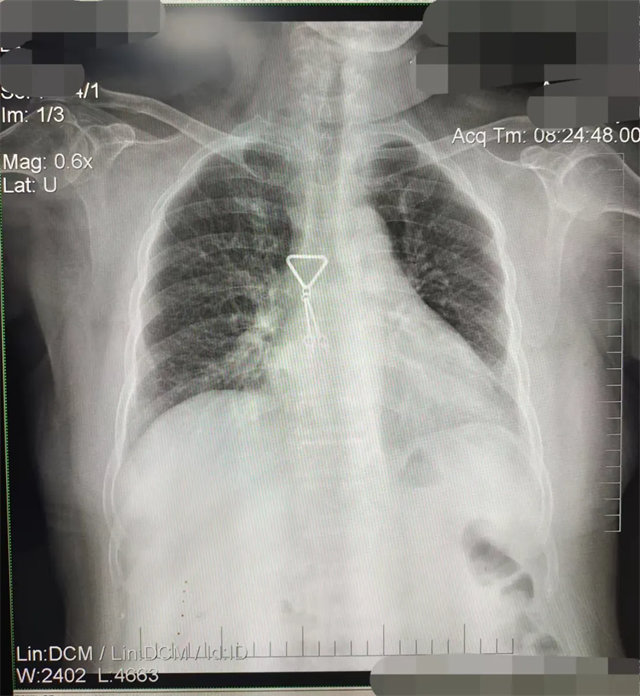

缺陷:两肩胛骨未拉开肺野之外,吸气不完全,且存在金属饰品遮挡。

解决:去除金属饰品及内衣后重新按标准体位摄片即可。